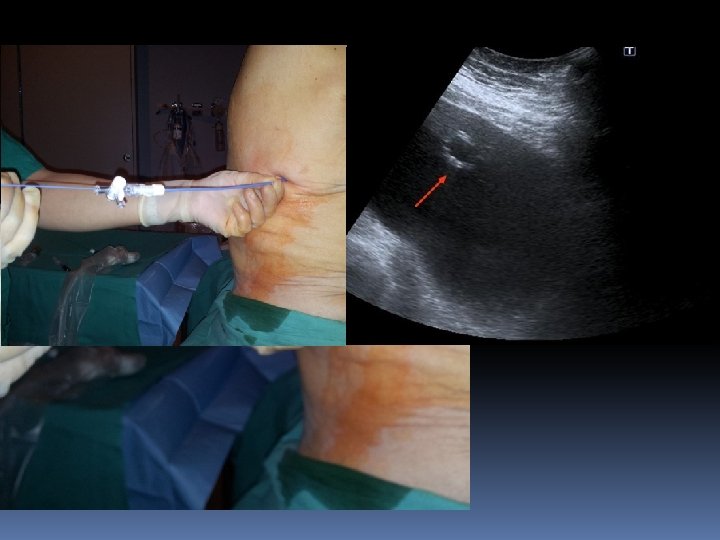

TECNICAS DE DRENAJE DE COLECCIONES Técnica trocar: • • Punción única Más rapida Menos segura Grandes colecciones Técnica Seldinger: • Menos rápida • Muy segura • La más utilizada

Povidona yodada Fisiológico 2 jeringuillas de 20 cc Gasas Bisturí Lidocaína 2% Aguja de 19 G Guía extrarrígida de soporte Dilatadores fasciales (7, 8 , 9) Catéter hidrofílico pig-tail 8 F

ELECCION DEL PUNTO DE ENTRADA • Siempre guiados por imagen ( US o TC ) SE • DESACONSEJA MARCAJE PARA PUNCION DIFERIDA Siempre por el borde superior de la costilla • Siempre el punto más declive • Evitar accesos dorsales posteriores si se puede • Evitar el borde medial de la escápula

COMPLICACIONES • Posicionamiento inadecuado (la + frec) ……………. Comprobar con TC • Lesiones de estructuras vecinas ( trócar) …………. Siempre Seldinger • Hemorragias autolimitadas (art intercostal o mamaria) • Bacteriemia transitoria • Reacción vasovagal • Edema pulmonar (> 1500 ml)